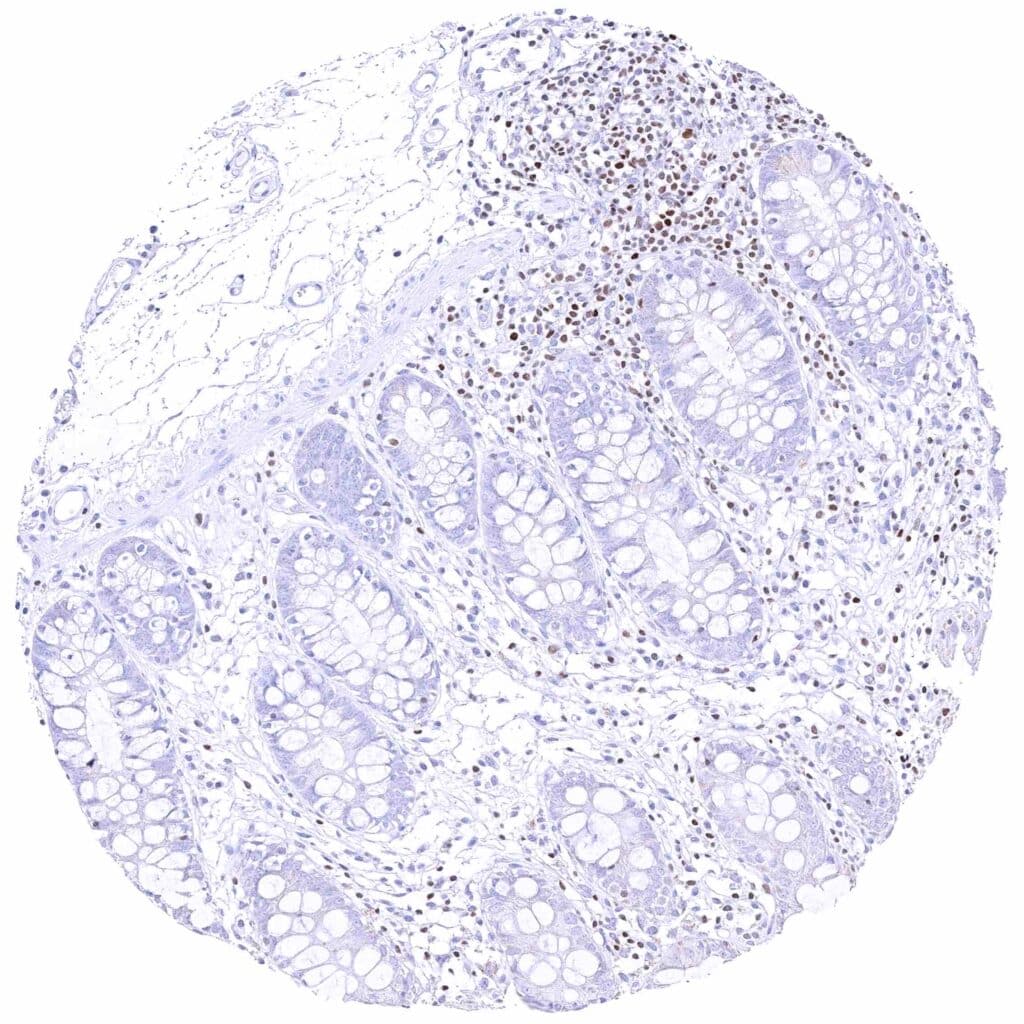

Colon descendens, mucosa – Nuclear GATA3 positivity of few lymphocytes. Faint cytoplasmic GATA3 positivity of some epithelial cells.

Rectum, mucosa – Nuclear GATA3 positivity of many lymphocytes.

Rectum, mucosa – Nuclear GATA3 positivity of some lymphocytes. Granular cytoplasmic GATA3 staining of epithelial cells.